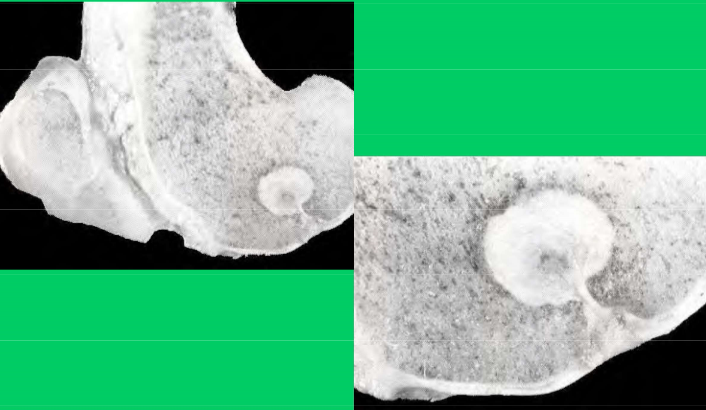

What is this lesion

OCD of the distal intermediate ridge of the tibia in the hock